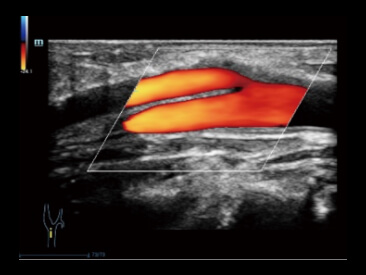

iClear

Функция используется для усиления и более четкого представления границ изображения в результате снижения шумов. Алгоритм подавления шума и артефактов от компании Mindray — iClear работает в 3D/4D режимах.

На изображении плечевой сустав: 1- Более подробная информация о мышцах; 2- Лучшее определение сухожильных волокон.